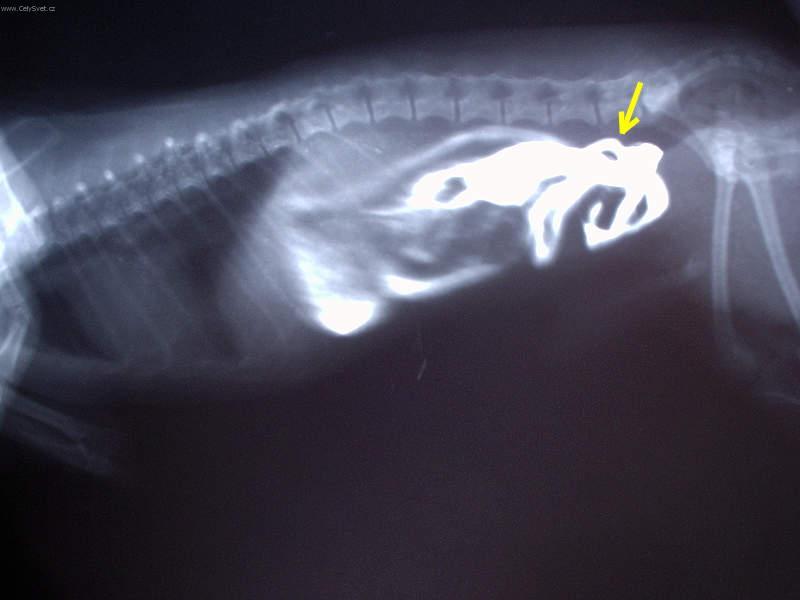

Fotogalerie > KOČIČÍ SVĚT: Veterinární poradna > Léčba interních onemocnění